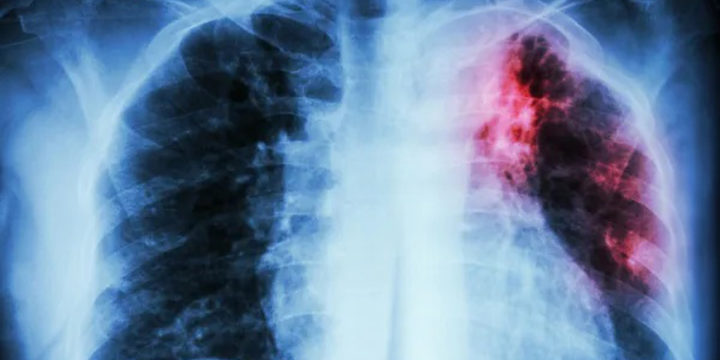

Novos casos de tuberculose batem recorde de 7,5 milhões em 2022

Novos casos diagnosticados de tuberculose em 2022 atingiram 7,5 milhões, o maior número desde que começaram a ser notificados, anunciou nesta terça-feira (7) a Organização Mundial da Saúde (OMS).

No ano passado, “a tuberculose foi a segunda doença infecciosa que mais matou em todo o mundo, depois da covid-19”, “a principal causa de morte de pessoas com HIV e uma das principais relacionadas à resistência antimicrobiana”.